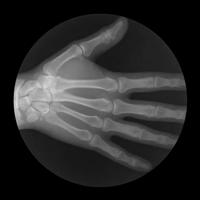

全身的关节与关节间有个空隙,叫关节腔,里面充满着保护、润滑关节的液体,而液体中还存在一些空气。

当关节受到拉或折的力时,关节腔内会形成新的空隙。此时液体中的空气会迅速往空隙内扩散,形成气泡并且破裂,于是发出声响。